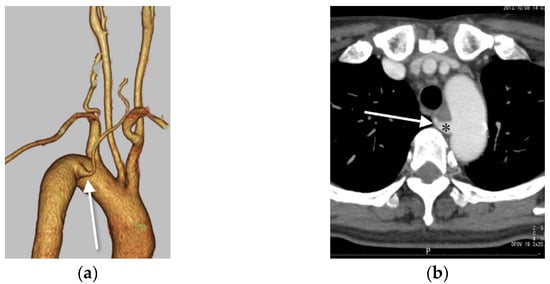

3.1. Right VA Originating from the Aortic Arch (Aortic Origin)